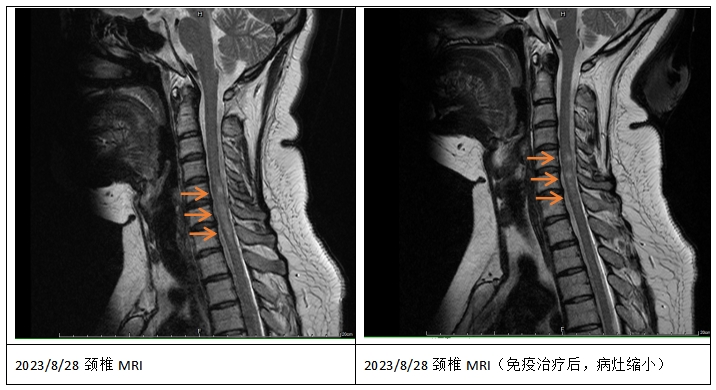

半年前,娇娇身体麻木不适的感觉加重了,再次住院时发现脊髓内又有新发较大面积脱髓鞘病灶,这次特异性抗体AQP4不仅仅在血里面存在了,脑脊液里也有1:3.2的滴度。常规的免疫球蛋白和激素治疗后,她的身体反应依然不佳。

瑞金医院风湿免疫科对于干燥综合征的治疗有丰富的经验和手段。随即,娇娇就被转到总院的风湿免疫科住院进行治疗。一个疗程后,娇娇的整体病症得到了明显控制,病情终于稳定了。